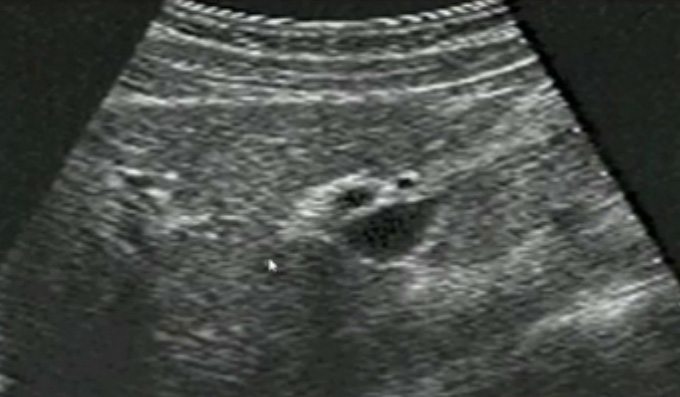

一、正常膽囊超聲圖像有的時候經(jīng)常發(fā)現(xiàn)檢查不到膽囊,其實(shí)有幾種可能性,檢查人員的技術(shù)不過關(guān)沒發(fā)現(xiàn)膽囊,就要找上級醫(yī)生會診,如果還是沒找到的話就不是技術(shù)問題。結(jié)石或腫瘤充滿膽囊,使其液腔消失,慢性膽囊炎使得膽囊萎縮或膽囊壁肥厚而囊腔消失患者已進(jìn)食,膽囊處于膽汁排空的狀態(tài),膽囊先天性過小或缺失;膽囊位置極端異常(可能很低或位于左側(cè))膽囊切除術(shù)后(注意詢問病史)。